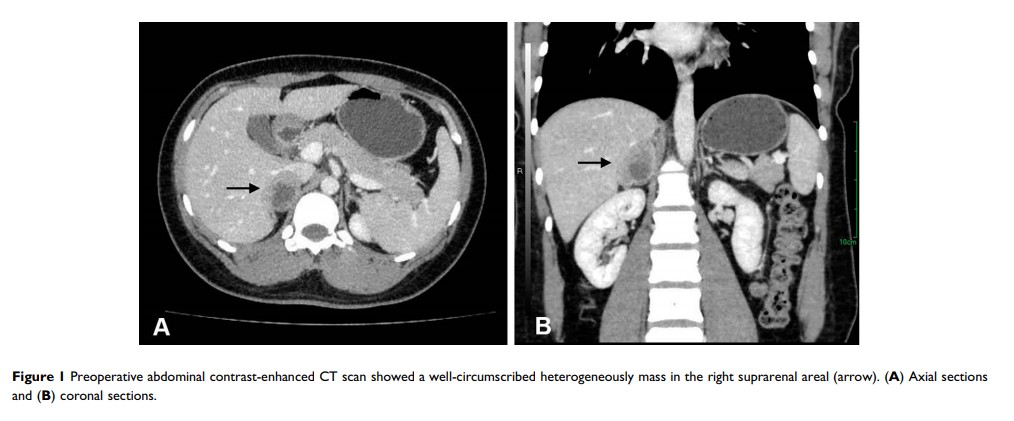

一名年轻女性的肾上腺区多形性平滑肌肉瘤:一个病例报告和文献回顾